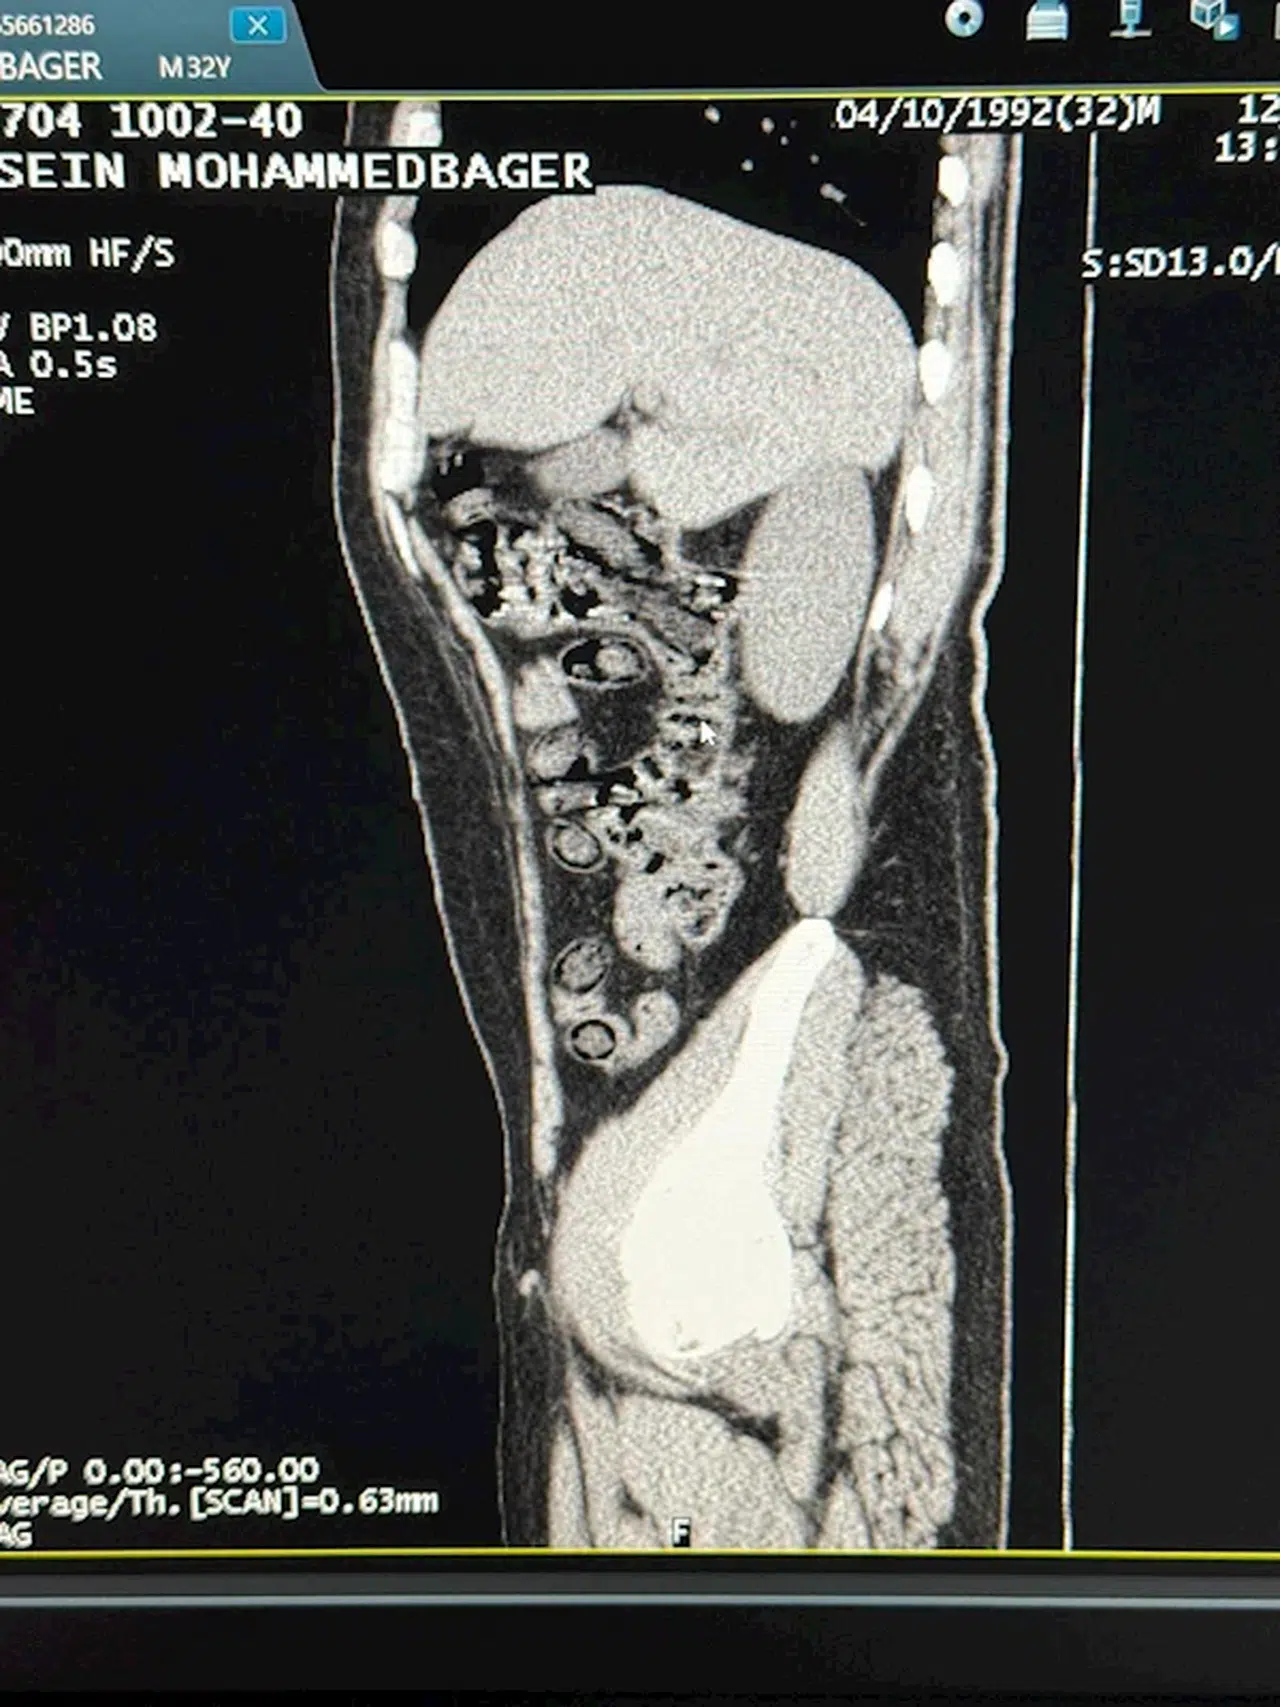

Muhammed Sami MARAL/ MUŞ, (DHA)- MUŞ’ta İran uyruklu 2 kişinin midelerinden 94 adet kapsül halinde 928 gram metamfetamin maddesi çıkarıldı.

Muş Emniyet Müdürlüğü Narkotik Suçlarla Mücadele Şubesi ekipleri, uyuşturucu madde nakli gerçekleştirdiklerinden şüphelendikleri İran uyruklu 2 kişiyi gözaltına aldı. Yapılan sorgulama sırasında davranışlarından şüphelenilen İranlı 2 kişi, hastaneye götürüldü. Burada çekilen tomografi sonucu şüphelilerin uyuşturucu madde yuttukları belirlendi. Hastanede yapılan müdahale ile 2 şüphelinin midesinden 94 adet kapsül halinde toplam ağırlığı 928 gram metamfetamin çıkarıldı. İşlemlerinin ardından adliyeye sevk edilen şüpheliler, nöbetçi sulh ceza hakimliği tarafından ‘uyuşturucu ve uyarıcı madde ticareti’ suçundan tutuklandı.